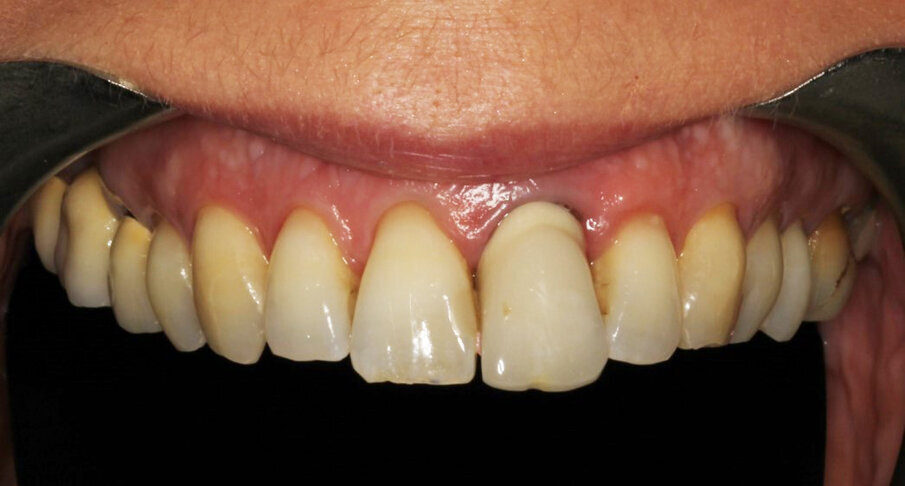

1. Full frontal view intraoral photograph (Fig. 2).

This sequence allows one to view immediately the presence of orthognathic and periodontal issues (Figs. 1 & 2), to evaluate the biotype (Figs. 2 & 3) and to estimate aesthetic challenges, like tooth colour, tooth texture, soft tissue/lip exposure and position of the incisal edge/lip (Figs. 2 & 4–6). The 3D intraoral scan is extremely helpful for determining orthodontic alignment of the teeth and in our protocol replaces an occlusal and/or 12 o’clock photograph in most cases.

The female patient, aged 47 and a non-smoker, was in good general health. She performed regular oral hygiene and had good periodontal health. The patient experienced increasing mobility of the maxillary left central incisor and complained about compromised aesthetics due to the extrusion and progressive migration of the tooth in a buccal direction. The incisor had been treated with a crown at a preadolescent age after a violent trauma. The intraoral radiograph showed incomplete root development and evidence of a root canal therapy suggesting a strip perforation though no signs of periapical lesions were present. The shape of the crown was not symmetrical in relation to the triangular shape of the maxillary right central incisor, but had a wider and rectangular profile. Minor general gingival recession had led to the presence of a tiny inter-dental space. The marginal gingiva was reddened, and the central papilla was not symmetrical.

The photographic aesthetic evaluation showed that it would be very difficult to obtain symmetry in tooth shape and have good-looking and healthy soft tissue support at the same time. The patient’s maximum smile exposed the gingival contours. In such cases, it may be wise to consider also the possibility of altering the anatomy of the contralateral tooth with, for example, a ceramic veneer and discuss outcomes with the patient before finalising the treatment plan. This can be evaluated by performing the cut/copy/flip/paste sequence in reverse (Fig. 7). Together with the patient, it was decided to start performing the best possible replacement of the maxillary left central incisor and evaluate at an advanced stage with a temporary crown on the implant and mature, conditioned tissue whether to add a veneer to the maxillary right central incisor.